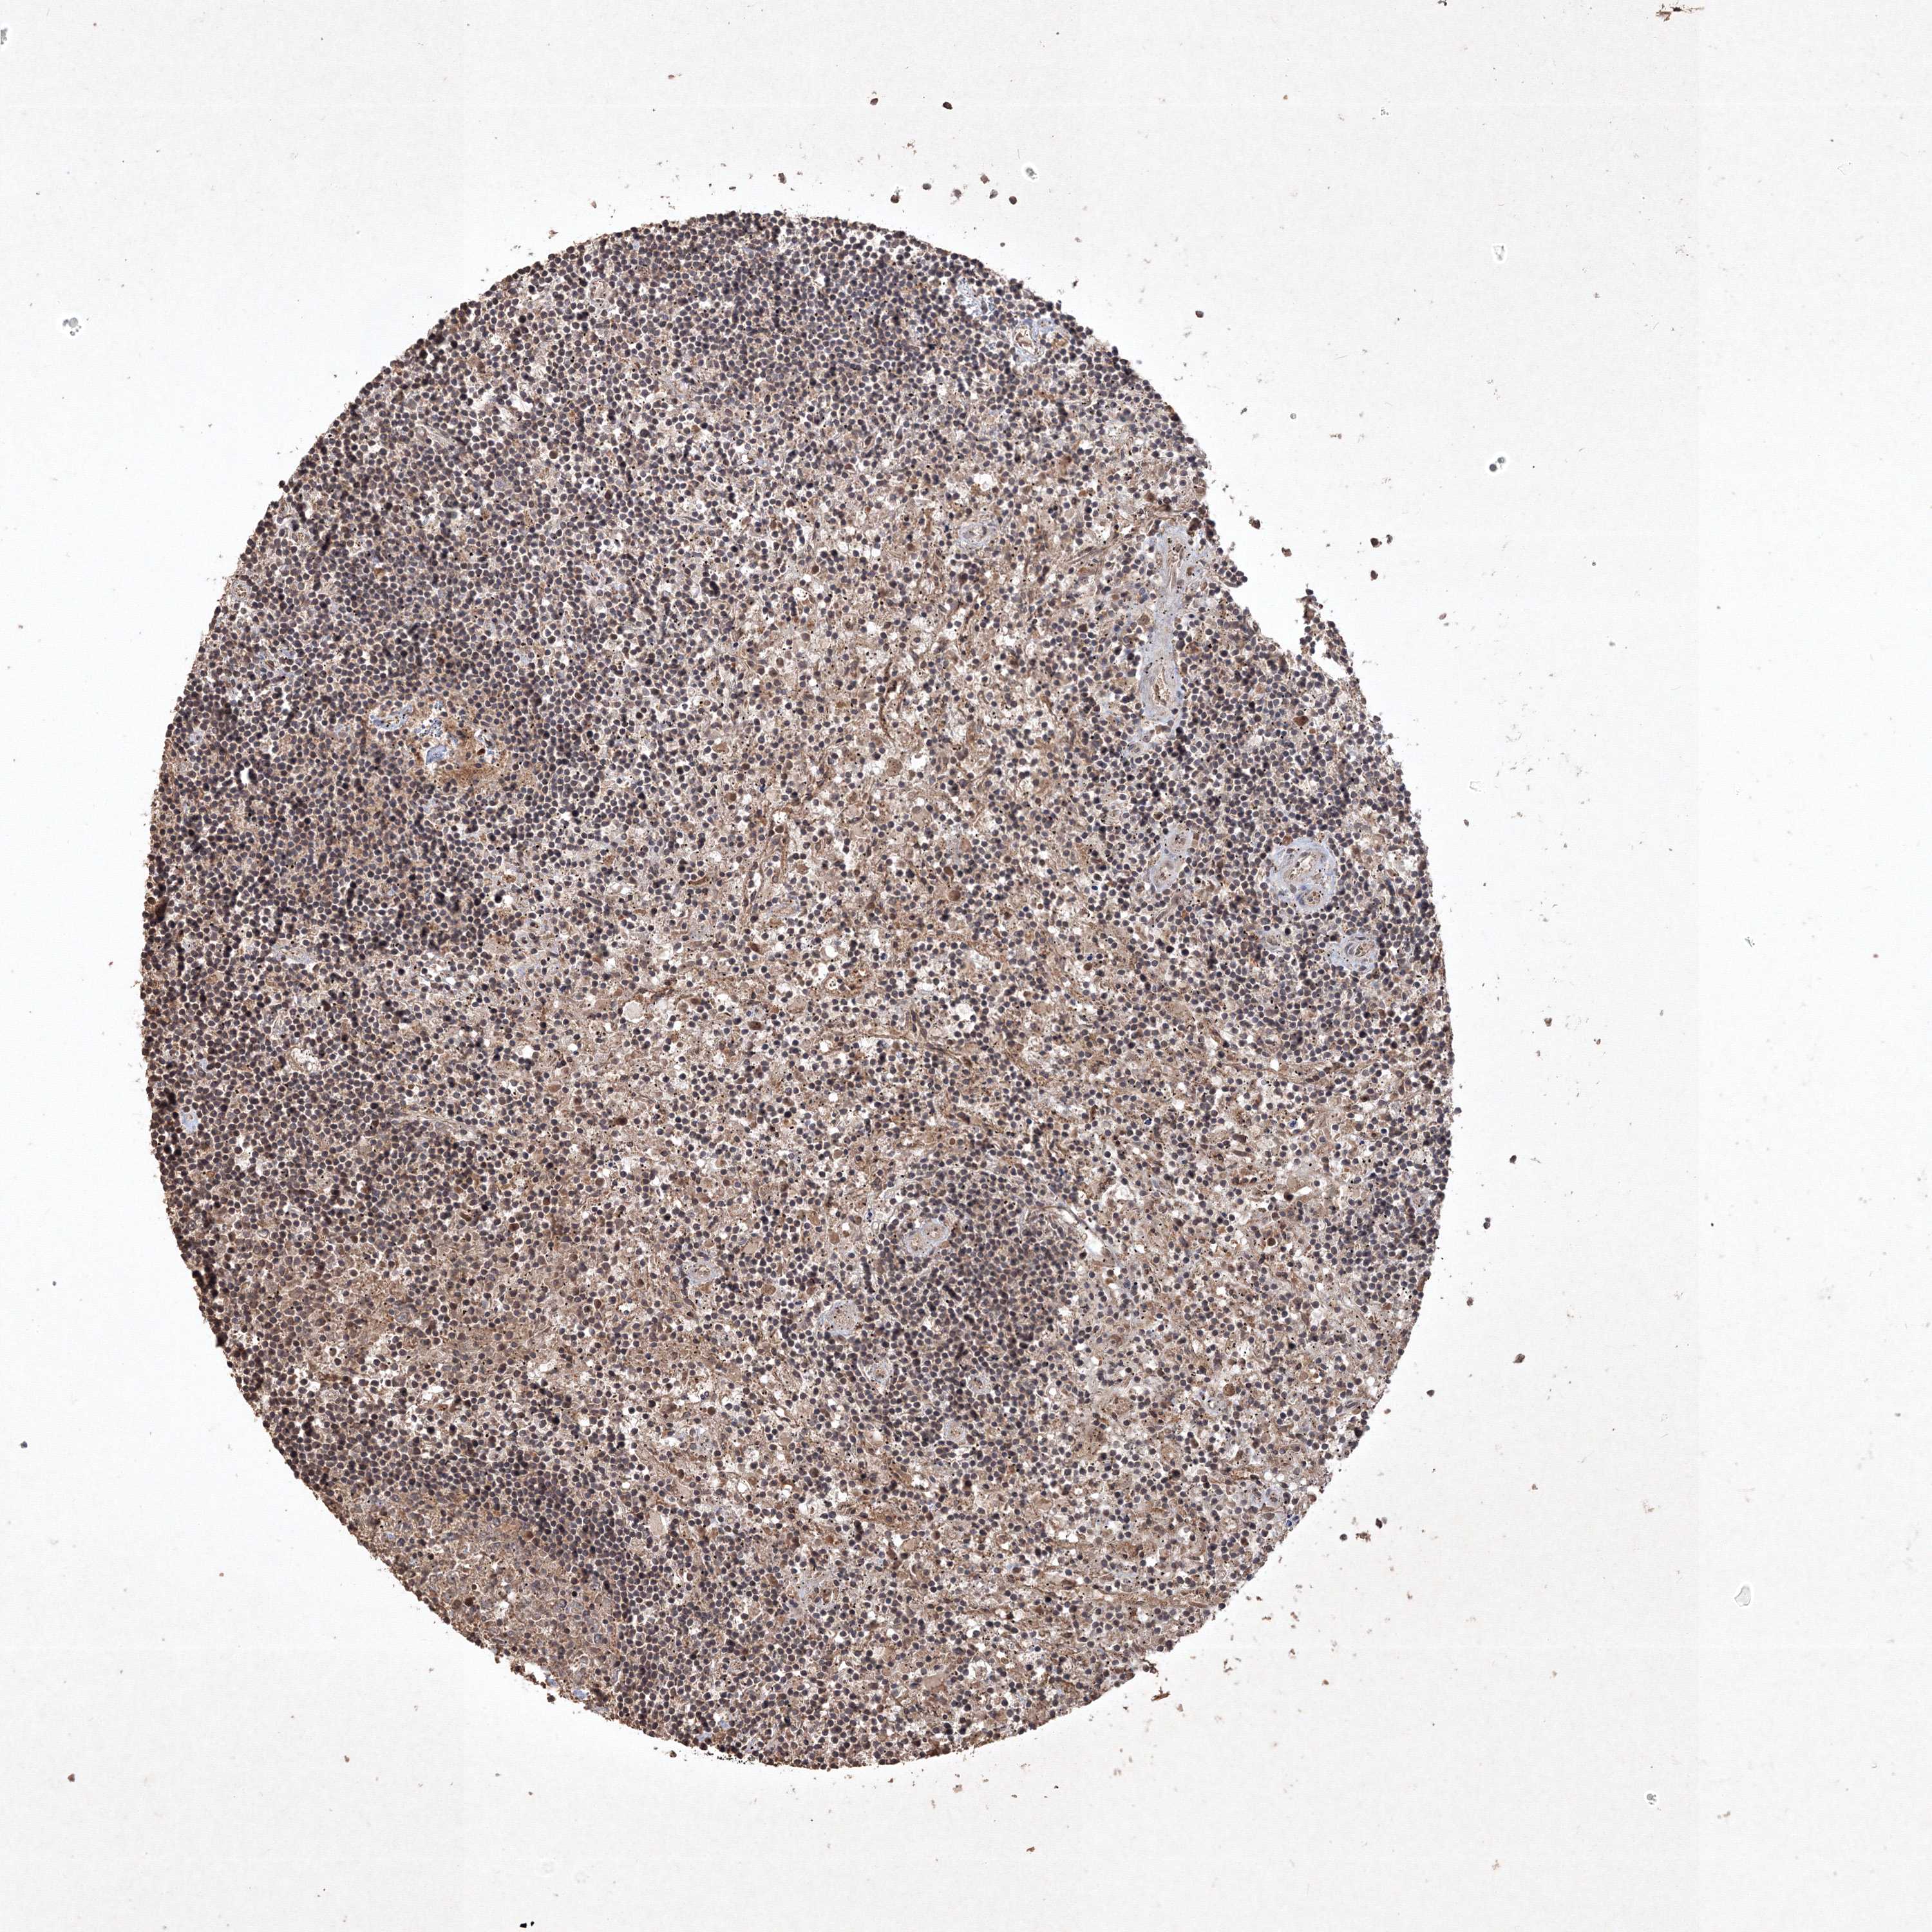

LYMPHOMA - Protein expressioni

A mouse-over function shows sample information and annotation data. Click on an image to view it in a full screen mode. Samples can be filtered based on level of antibody staining by selecting one or several of the following categories: high, medium, low and not detected. The assay and annotation is described here.

Each image is clickable and will lead to virtual microscopy that enables deeper exploration of all samples and also displays staining intensity scores, fraction scores and subcellular localization as well as patient and tissue information for each sample.

Antibody HPA062281

Staining

High

Medium

Low

Not detected

Intensity

Strong

Moderate

Weak

Negative

Quantity

>75%

75%-25%

<25%

None

Location

Nuclear

Cytoplasmic/membranous

Cytoplasmic/membranous,nuclear

Malignant lymphoma, non-Hodgkin's type, Low grade

Malignant lymphoma, non-Hodgkin's type, High grade

Hodgkin's disease, NOS